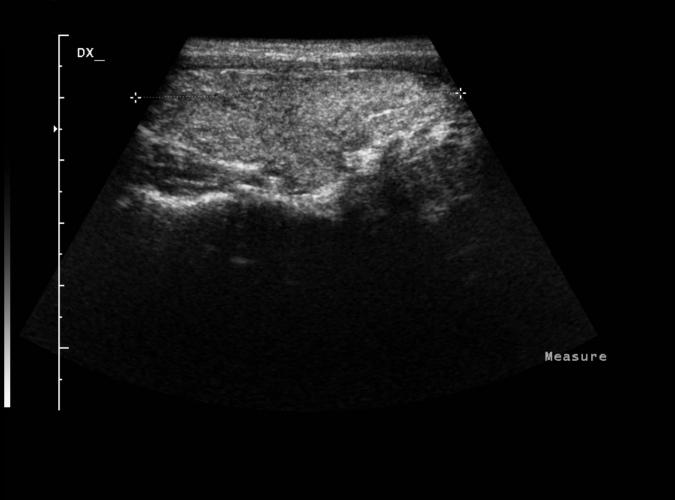

av Catherine Olsson, sonograf

Patologi.

Long. höger thyroidealob.

"Klassisk Hashimotothyroidit" ..se bild 9l